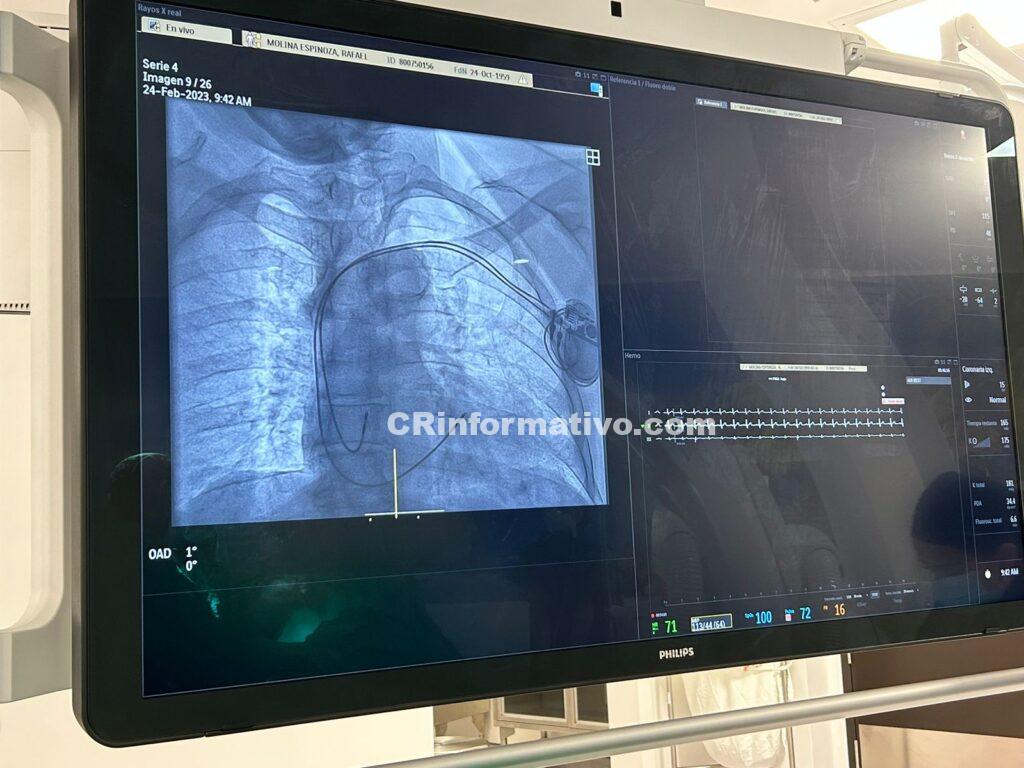

La Unidad de Hemodinamia del centro Servio Flores Arroyo del hospital San Rafael (Alajuela) inició este viernes con la colocación de los primeros tres marcapasos a pacientes con enfermedad cardiovascular.

El doctor Harold Hernández Matamoros, cardiólogo intervencionista de este hospital, explicó que el primero fue un marcapasos bicameral a un paciente que tenía disfunción atriventicular, defecto del conducto auriculoventricular, un tipo de defecto cardíaco congénito.

- Se colocaron tres marcapasos a dos pacientes adscritos al hospital de Alajuela y uno al hospital de Cartago con resultados satisfactorios.